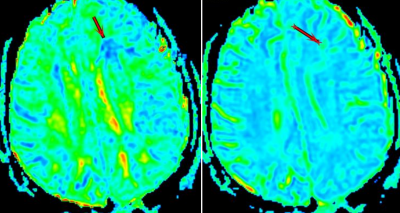

There were significant differences in FA ,MD and MK between the two groups (P <0.01). The ROC curve comparison analysis was displayed in Table 1. The area under ROC curve (AUC) of MK value was 0.848, and the sensitivity and specificity were 72.5% and 85.0%, respectively. The AUC curve of FA value was 0.804, and the sensitivity and specificity were 60.0% and 90.0%, respectively. The AUC of MD was 0.702, and the sensitivity and specificity were 50.0% and 87.5%, respectively(Tabe1, Figure 2).

Fig2